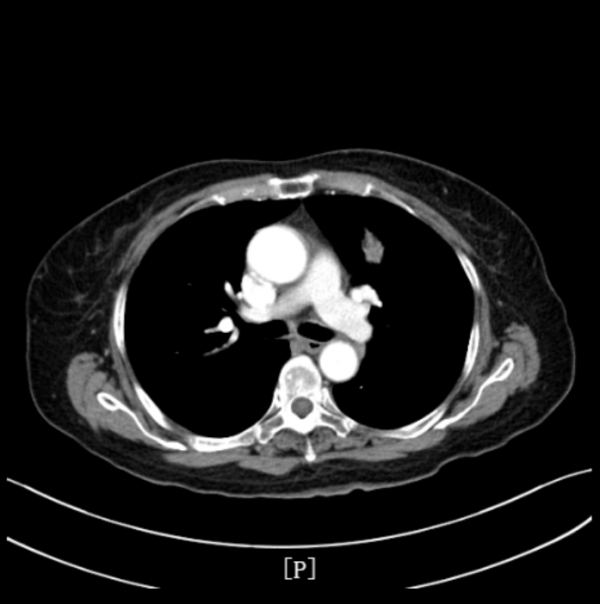

▎入院影像學檢查:

- 肺部CT檢查提示:左肺上葉前段佔位性病變,伴遠端阻塞性炎症及肺不張,考慮:周圍型肺癌可能性大。

治療後安排患者複查肺部CT,提示左肺腫瘤性病變較前明顯縮小。療效評估PR。

該患者2021年5月因“咳嗽咳痰伴發熱10余天”入院,完善肺部CT檢查提示:左肺上葉前段佔位性病變,伴遠端阻塞性炎症及肺不張,考慮:周圍型肺癌可能性大。頭部MRI檢查提示:雙側小腦半球點狀異常強化灶,考慮轉移瘤病灶。雙側大腦半球及小腦半球腦溝鑄型明顯異常強化,考慮肺癌軟腦膜轉移。腦膜轉移較腦實質腫瘤轉移少見,但肺癌腦膜轉移患者預後更差。患者在2021年6月進行支氣管鏡檢查,取腫瘤組織病理檢查也證實,其左肺上葉佔位系肺腺癌。入院診斷:左肺上葉肺腺癌伴腦轉移。分級:T2NxM1c IV期。

根據《CSCO 2021非小細胞肺癌診療指南》推薦,治療組給予患者培美曲塞二鈉化療+貝伐珠單抗全身治療。直至患者完成三個週期聯合治療後,複查胸部CT提示:左肺上葉腫瘤病灶較前明顯縮小。且治療期間不良反應經對症治療後迅速緩解,患者耐受性良好。